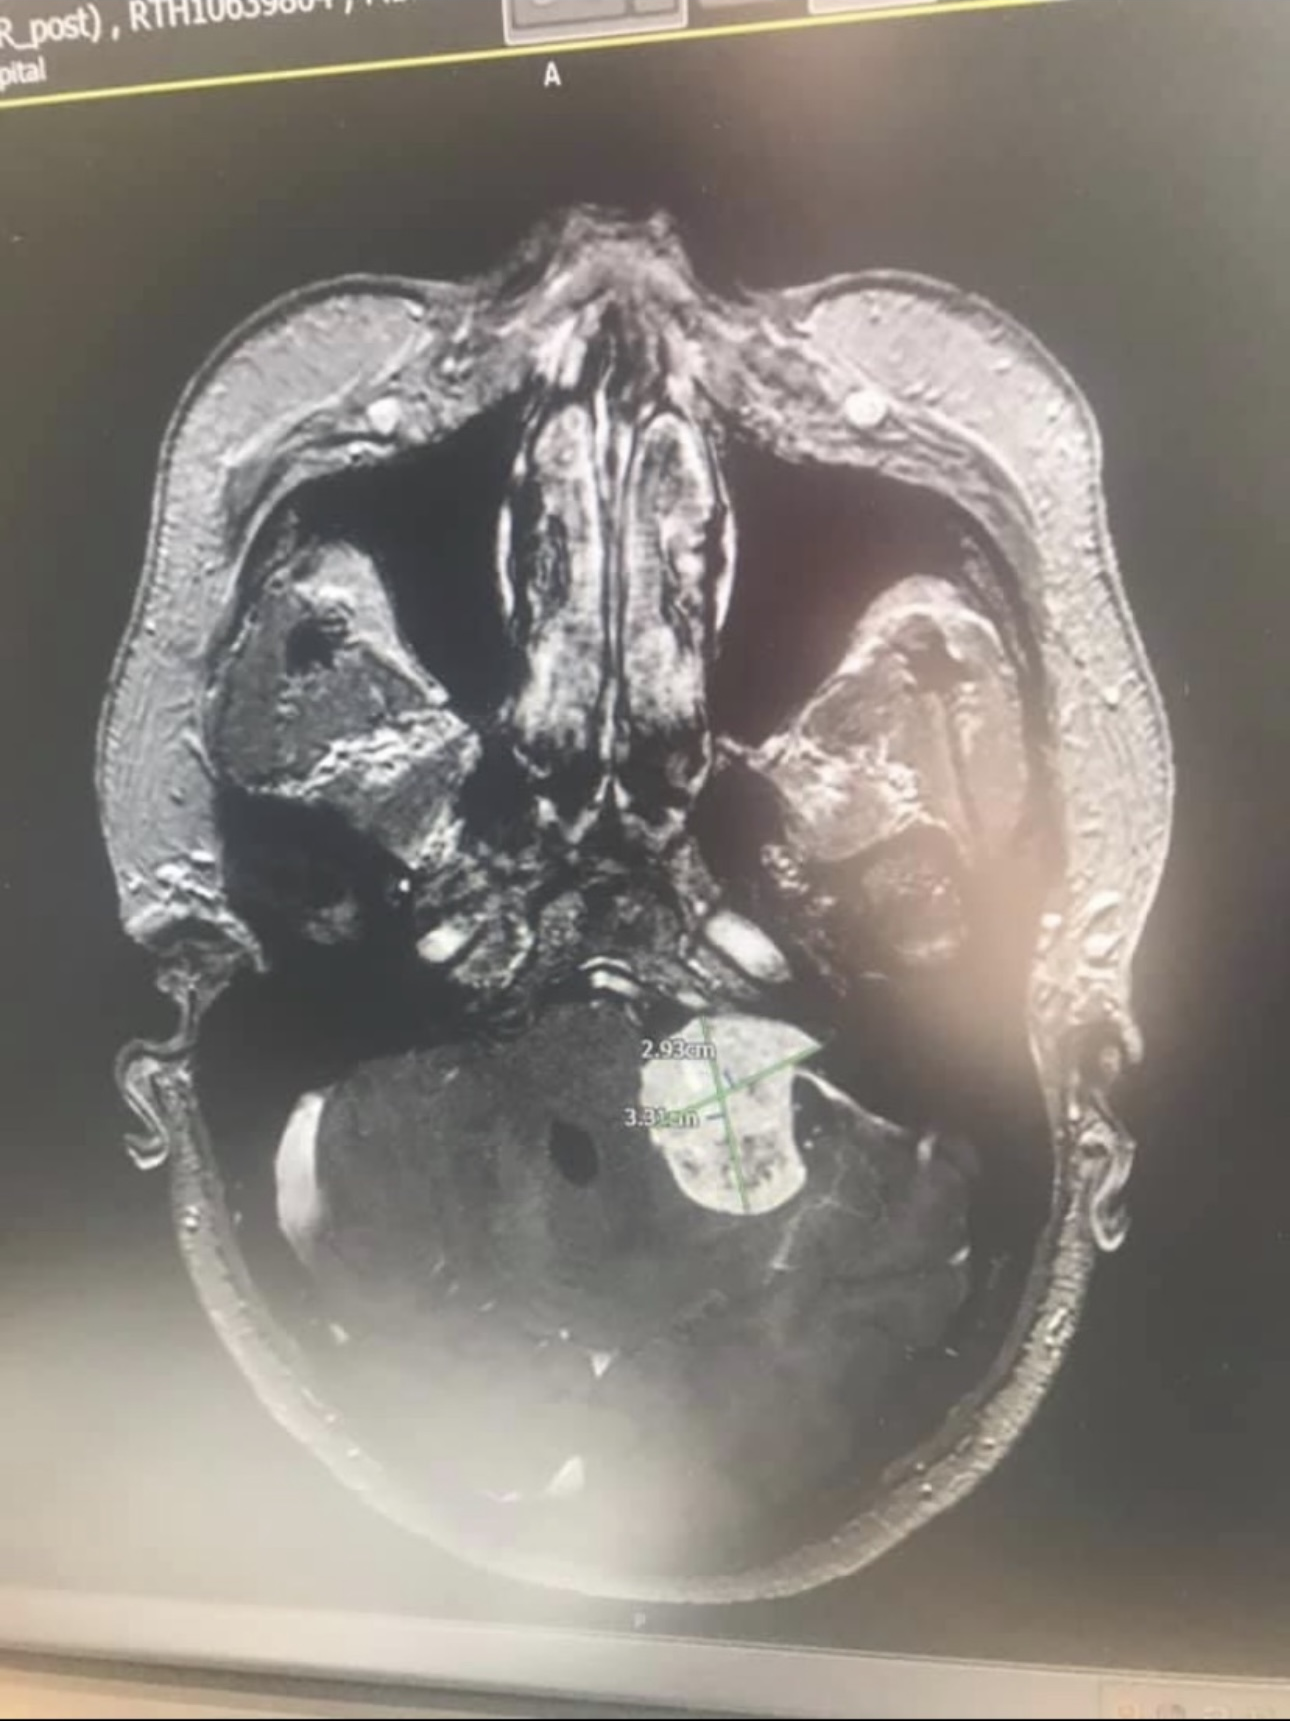

In June 2024, just three weeks before I was due to finish my nursing degree, I received a life-changing diagnosis: a low-grade brain tumour. At the time, I was juggling clinical placements, coursework, and plans for my future in nursing. But looking back, the signs were there. I had been suffering from intense headaches and migraines, tingling down the right side of my body, and moments of clumsiness and imbalance. I brushed most of it off — telling myself it was probably stress, or maybe I’d just bumped myself.

My care began in Nottingham, where I was completing my training. Instead of the summer I had planned, I spent it going from appointment to appointment, from scan to scan. It was overwhelming, but I tried to stay focused. I knew I wanted to move back to Yorkshire to be closer to family and to start my new grad nursing job — a job I was genuinely excited about.

Once I moved back home, my care was transferred to Leeds, the nearest major hospital. I met my neurosurgeon in December 2024. Because the tumour’s exact nature was uncertain and the location delicate, we agreed that an awake craniotomy would be the safest route. It was terrifying — but I trusted the team, and I was determined.

In February 2025, I underwent a 9-hour awake craniotomy. The surgery was successful. The tumour was completely removed. I thought the hardest part was behind me.